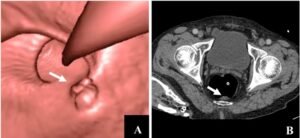

Virtual colonoscopy, also known as CT colonography or CTC, is a non-invasive imaging technique used to visualize the inside of the colon and rectum for